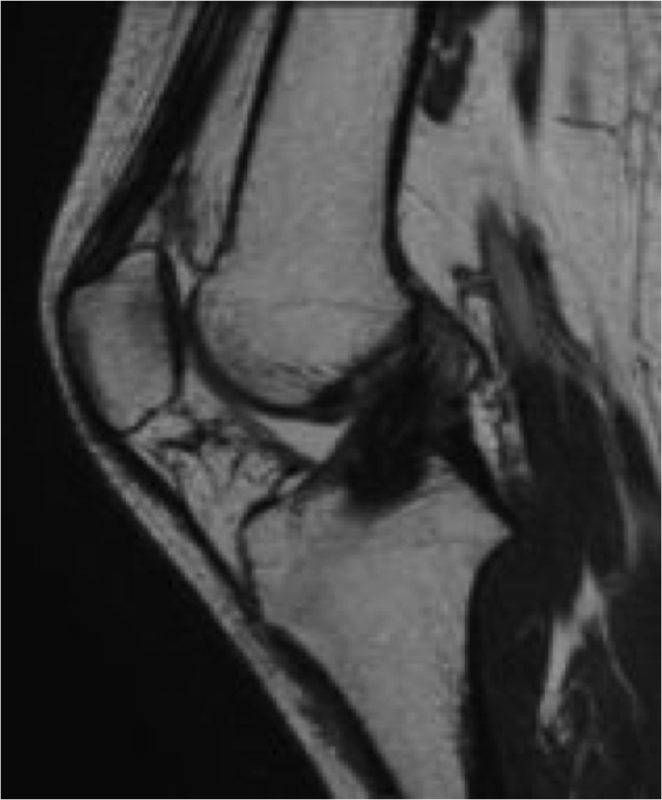

MRI

術前術後

ACLの連続性がなく、途絶している。再建靭帯の成熟を認める。